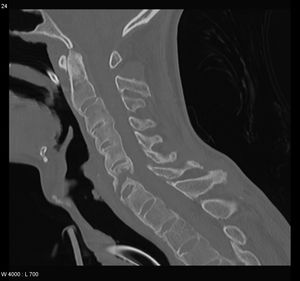

يبدأ التهاب الفقار المقسط في صغار البالغين بألم مبهم في أسفل الظهر، ويبوسة مديدة تالية للراحة تتحسن جزئياً بالحركة والتمارين الرياضية. ينتشر الألم إلى الاليتين والقسم الخلقي من الساقين. كما يحدث ألم في القفص الصدري بإصابة المفاصل الغضروفية المركزية فيه، وقد يكون لهذا الألم صفات جنبية، ويظهر الألم أيضاً في مفاصل قبضة القص Manubriosternal والمفاصل القصية الترقوية. إن التهاب ارتكازات الأربطة والأوتار عرض بارز وقد يكون العرض الأول. وينجم الألم عن التهاب الأصابع Dactylitis ' أو وتر أشيل، أو اللفافة الأخمصية، أو عرف الحرقفة iac أ I Crest. تكون الإصابة المفصلية بشكل الام مفصلية، أو التهاب مفاصل عديد، يصيب المفاصل الزليلة الدانية وبشكل غير متناظر كالكتفين والمرفقين والركبتين ونادرا المفاصل الصغيرة القاصية. وتترافق هذه الإصابة بيبوسة صباحية مديدة وأحياناً بتورم الا أنه من غير الشائع حدوث إصابة مفصلية تاكلية شديدة.

يحدث التهاب العنبية الأمامي في حوالي ربع المرضى، ويتظاهر بألم واحمرار وخوف من الضياء، وتكون هذه الإصابة نوبية، وحيدة أو ثنائية الجانب. يبدي الفحص السريري نقصاً في حركية العمود الفقري، مع فقد تام أو جزئي للقعس القطني الفيزبولوجي، وزيادة في الحدب الظهري. أما المظاهر المتأخرة فتشمل تحدد حركة جدار الصدر في الشهيق العميق (أقل من 2.5 سم) مع انحناء تدريجي، وثبات العمود الفقري والرأس في وضعية العطف. ويمشى المريض جاراً قدميه Shuffling Gait مع تفاوت شدة إصابة المفاصل المحيطة.[2]